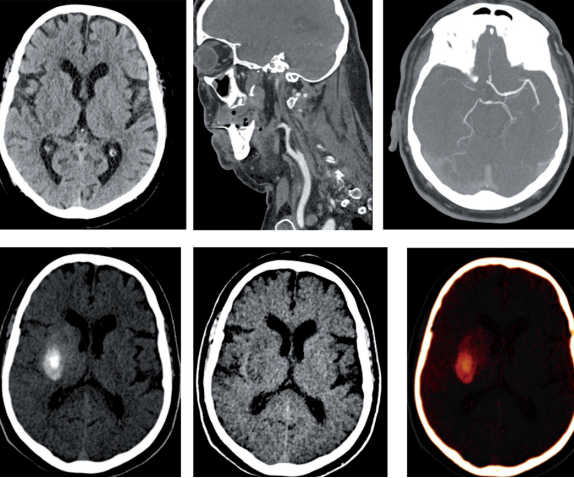

80–90keV VMI能区分正常和梗死脑实质

双能量CT有助于闭塞性颈动脉支架术后抗血小板方案选择